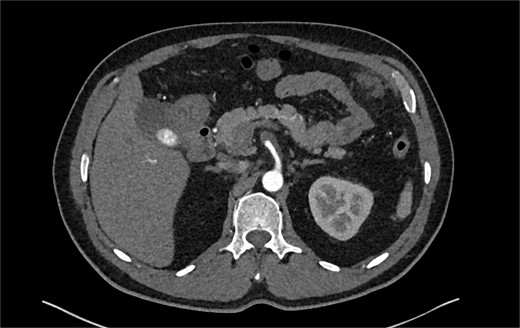

The patient was initially managed conservatively with blood pressure control and anticoagulation using Apixaban and aspirin. However, after one day of treatment, he experienced worsening abdominal pain and a hypertensive crisis with blood pressure reaching 228/113 mmHg. A follow-up CTA showed an extension of the SMA dissection extending into branch vessels, now associated with a small 1 cm aneurysm and hemoperitoneum (Fig. 2). Apixaban was stopped, and the patient was transitioned to a heparin drip, with an esmolol drip as needed for blood pressure control. As his symptoms improved, he was bridged back to apixaban and discharged on enoxaparin.

CTA demonstrating a more extensive SMA dissection extending into branch vessels. New hemoperitoneum most pronounced in the left abdomen with no active extravasation noted but probably arises from the left mesentery.